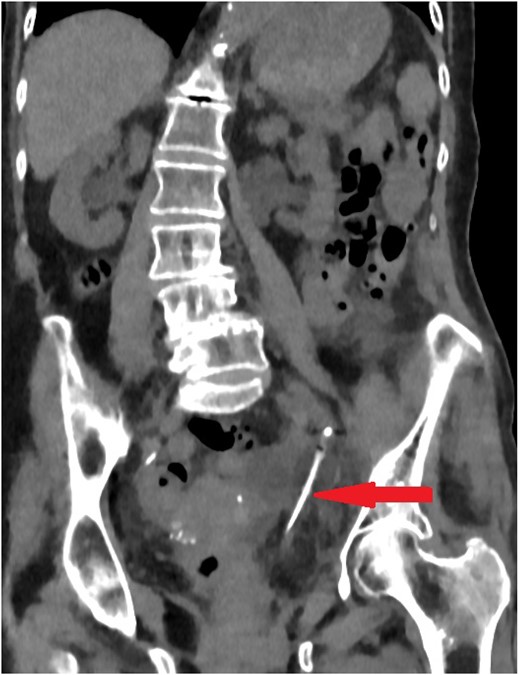

Luo et al. published a review included 23 cases of urethral catheter inadvertently placed into the ureter, 5 cases were caused by supra-pubic catheter [7]. Only three cases (13%) needed surgical repair (Fig. 4). Most of these cases had LTC secondary to neurogenic bladder, with female predominance (3:1). LTC might lead to contracted bladder, facilitating LTC to pass into the ureter in the presence of VUR. In addition, the short urethra in female might increase the risk of ureteric placement of LTC.

Luo et al. review: Only three cases (~13%) needed surgical repair. Three cases needed endoscopic deflation of the catheter balloon. Four cases needed urinary diversion, three with JJ ureteric stent and one with nephrostomy due to failed ureteric stenting. Thirteen cases were treated conservatively with simple catheter replacement.